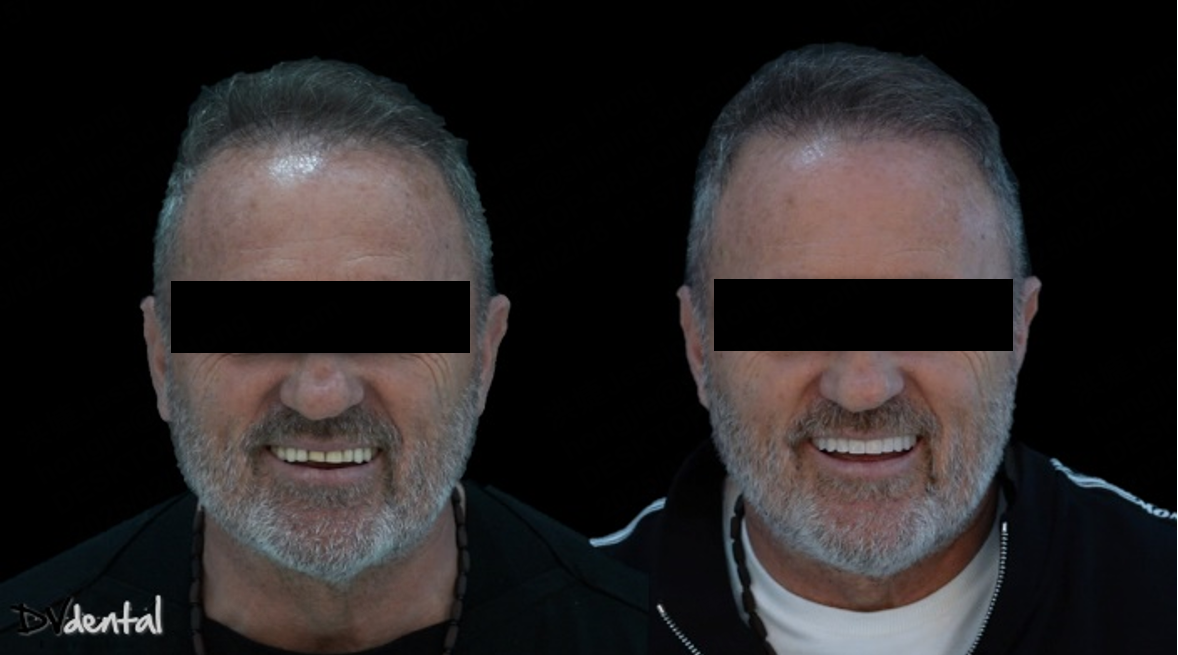

4. Try-in

Before the permanent prosthesis, a prototype of it has been created for intraoral try-in. This is a good way to check the fit of our prosthesis clinically and radiographically while assessing the aesthetics simultaneously. After the successful try-in, the manufacturing of the permanent prosthesis (Zirconia full contour on Ti bases) will proceed. Finally, periapical X-rays show that the permanent prosthesis fits excellently, and the aesthetic outcome was exactly as planned, the patient is really happy about the result.

Fig 22: The intraoral photos after treatment.

The Elite intraoral scanner, combine with IPG technology, provided a highly accurate digital impression for this case, laying the foundation for the implant restoration design. The MetiSmile face scanner thoroughly captured the patient’s facial morphology, ensuring the restoration’s harmony in both function and aesthetics, making it an essential tool in the occlusal reconstruction process.

This case highlights the significant advantages of digital technology in full edentulous implant restoration. Specifically, the combined use of the intraoral scan with IPG technology and facial scanning offers a precise, efficient, and personalized solution for complex occlusal reconstruction cases.